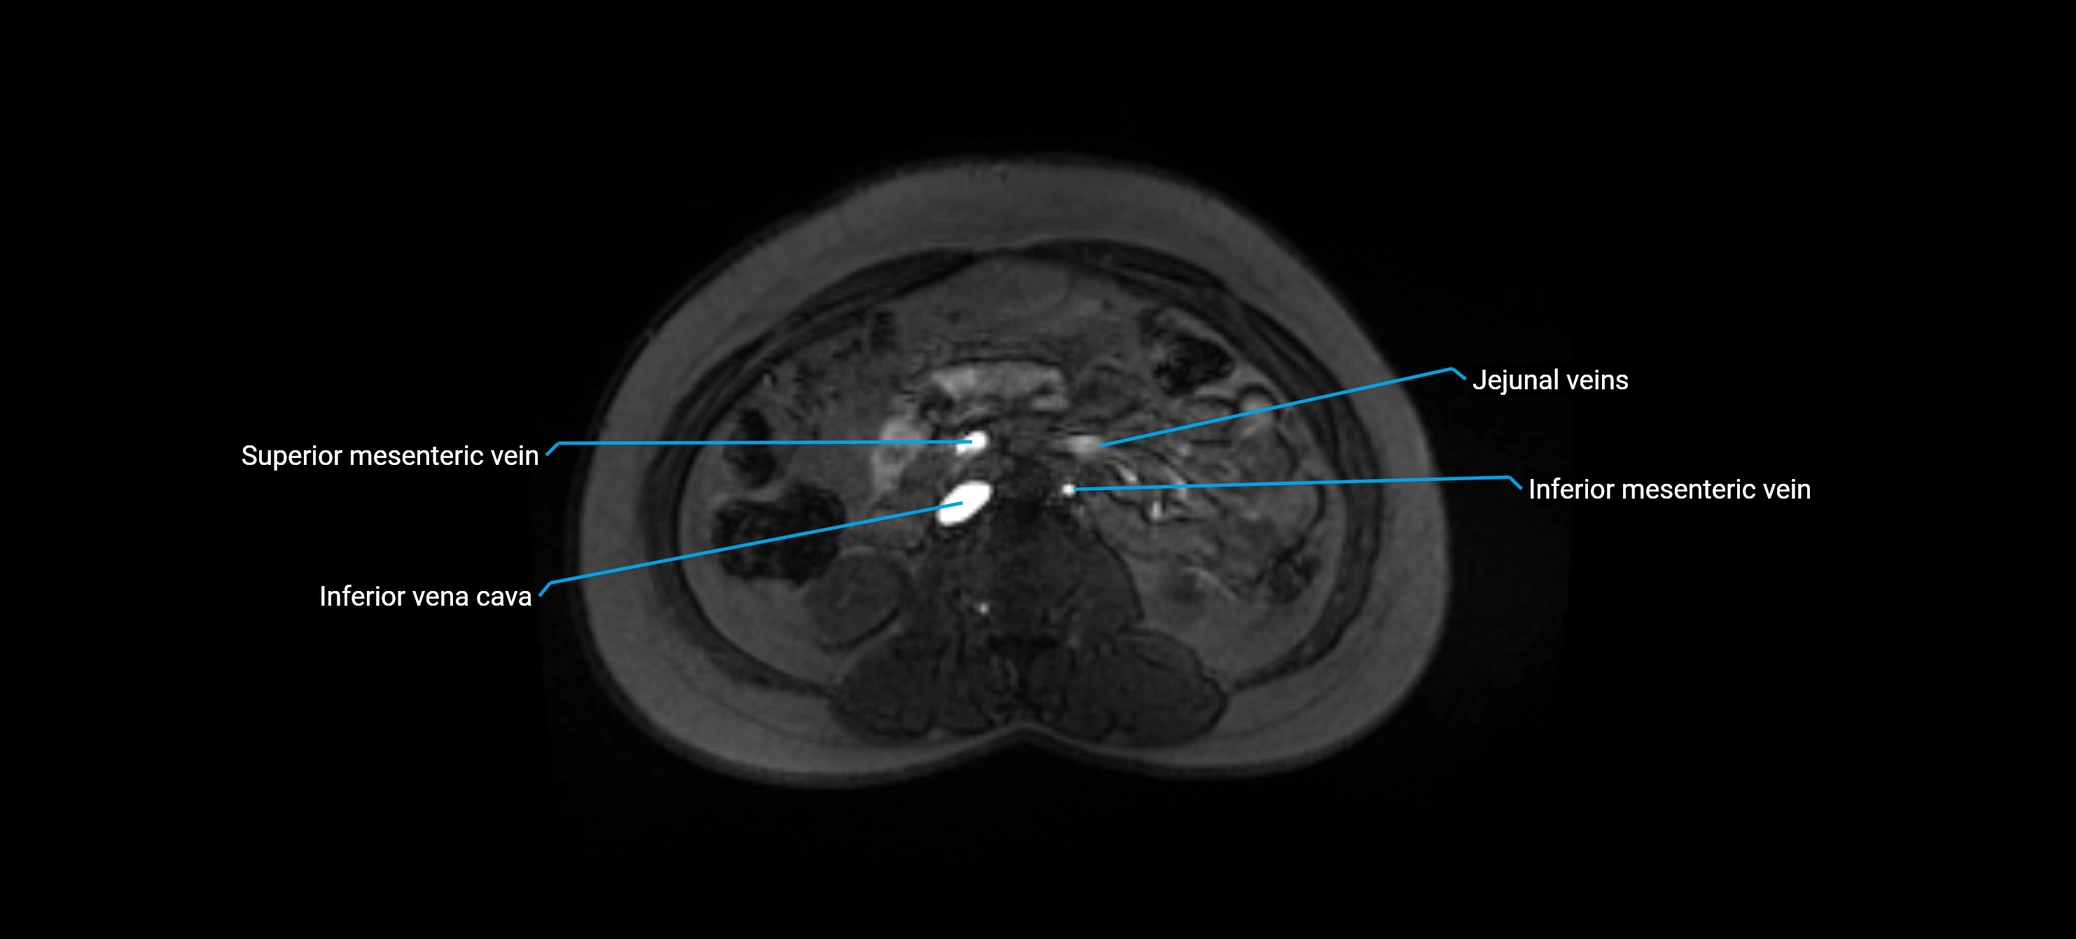

MRI image

image